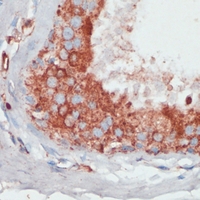

IHC (Immunohiostchemistry)

(Immunohistochemical analysis of PGK2 staining in human breast cancer formalin fixed paraffin embedded tissue section. The section was pre-treated using heat mediated antigen retrieval with sodium citrate buffer (pH 6.0). The section was then incubated with the antibody at room temperature and detected using an HRP conjugated compact polymer system. DAB was used as the chromogen. The section was then counterstained with haematoxylin and mounted with DPX.)